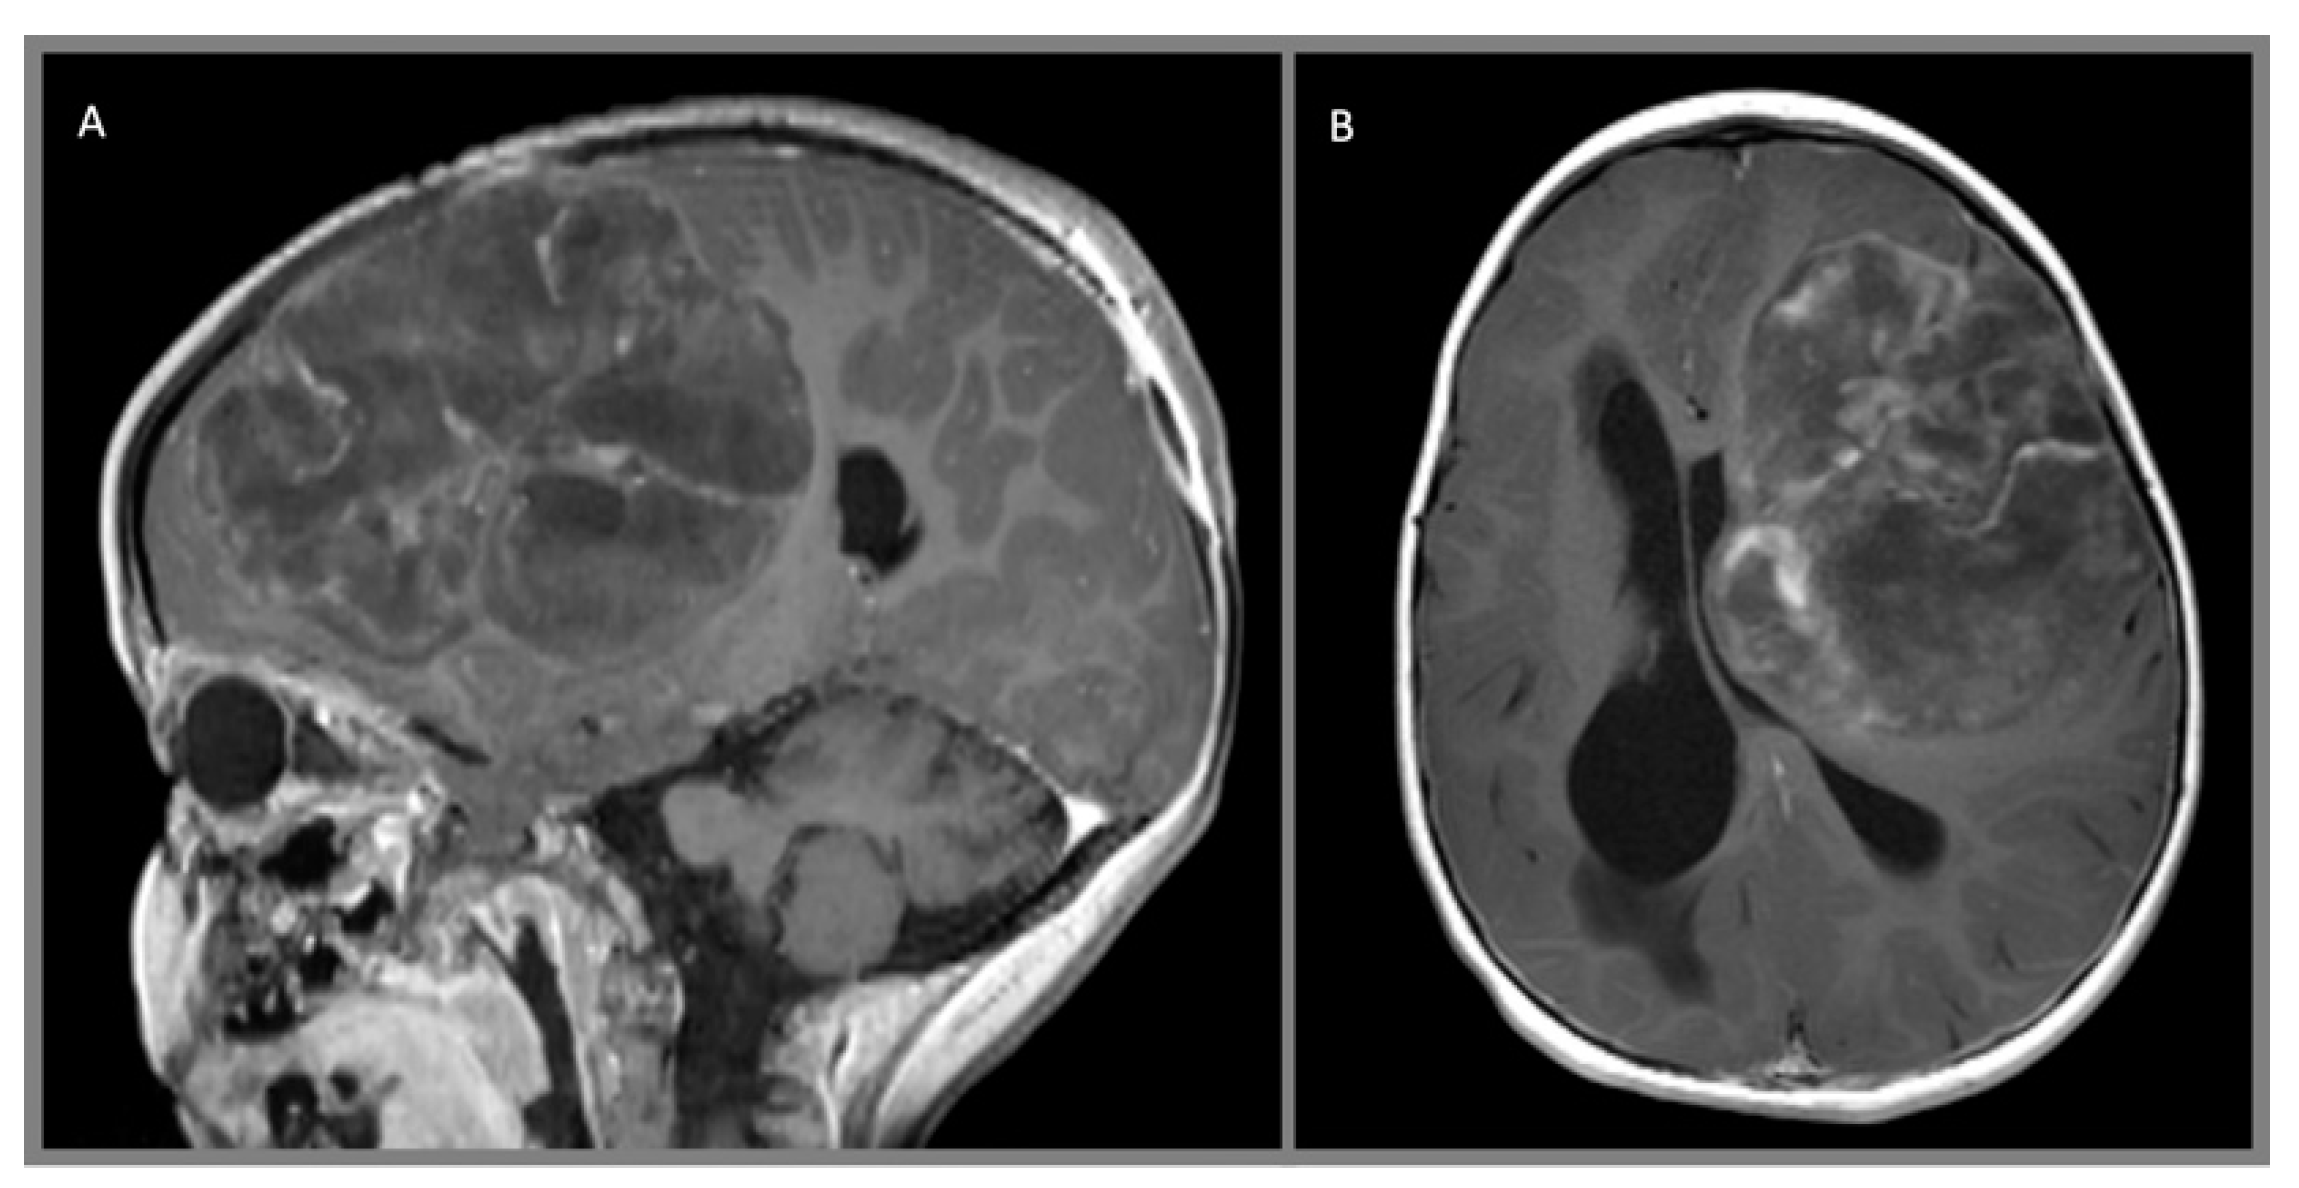

4. Diagnostic Studies